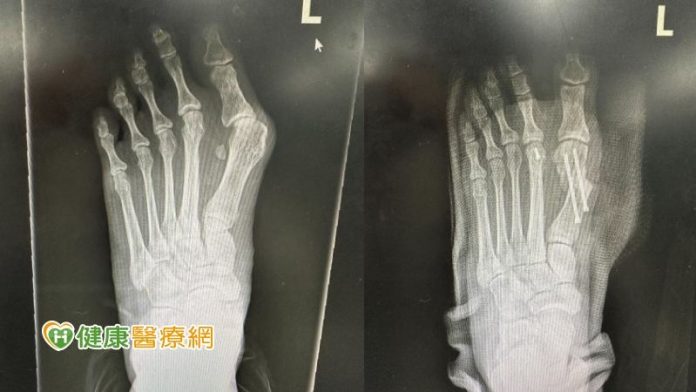

【健康醫療網/記者吳儀文報導】張小姐因工作關係每天需要穿著高跟鞋,大拇指內側長期與鞋面摩擦,半年前開始無法久站,走路不到半小時,腳底就痛到像火在燒,拇指呈現ㄑ字型根部又凸又腫,就醫檢查時拇趾已外翻將近40度。

「拇趾外翻」的患者腳背第一掌骨與大拇趾間的關節會呈現外凸彎曲。陳建樺醫師提到,拇指外翻常會伴隨其餘腳趾的擠壓變形、足部疼痛外翻,外觀上大拇趾會往第二拇趾偏移15度以上,使大拇趾、第二拇趾交疊,使第二拇趾異位,導致穿鞋時摩擦不適,大拇趾根部的骨頭突出且紅腫發痛。

陳建樺醫師表示,拇趾外翻初期可以先透過消炎止痛藥、改善穿鞋習慣,減輕病情惡化,不過無法根治外翻,當保守治療一段時間後疼痛感仍未緩解,病人可以考慮接受大腳趾外翻手術,矯正腳趾變形並重整腳趾平衡。